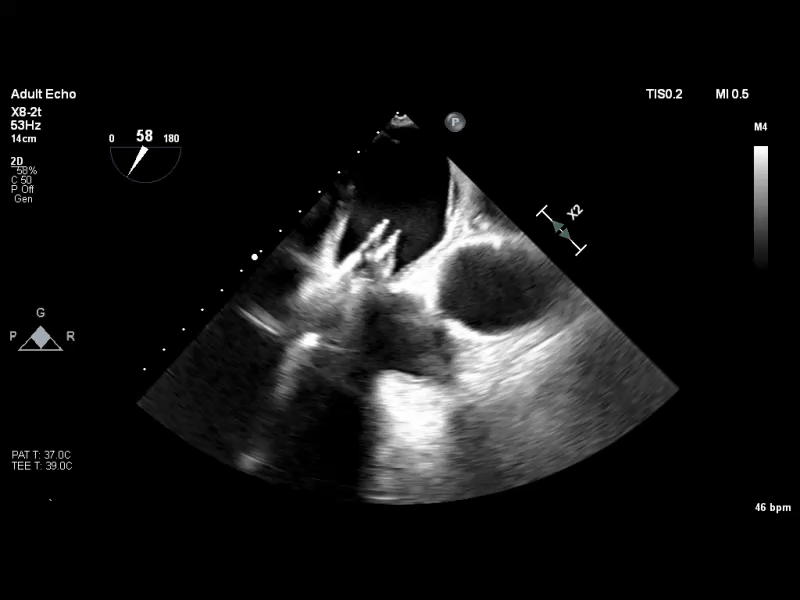

经食道超声心动图(TEE)提示:二尖瓣病变Carpentier II型,DMR,二尖瓣2区反流及P2腱索断裂并瓣叶脱垂,Gap 6 mm,Width 15 mm, 瓣口面积6.7 cm²,2区前叶长20 mm,后叶长19 mm。MR4+,反流束来自于2区,偏心性反流束,指向前叶;VC 11 mm。房间隔穿刺空间约4.5 cm。

术前TEE 3D

术前TEE XPLANE